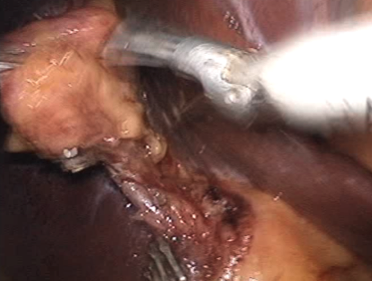

現在、胆石症の手術は、お腹に小さな穴をいくつか開けて行う腹腔鏡下胆嚢摘出術が一般的です。この手術は、従来の開腹手術に比べて、傷が小さく、術後の痛みが少なく、入院期間も短いという大きなメリットがあります。

当院では、患者さんの状態を十分に評価した上で、この腹腔鏡下手術を積極的に行っています。一部の特殊なケース(過去の開腹手術歴、重度の炎症、肝硬変など)では開腹手術が選択される場合もありますが、患者さんの負担を最小限に抑えるよう、できる限り腹腔鏡での手術を目指しています。また、傷の数を減らした単孔式手術など、より体にやさしい手術にも取り組んでいます。

まずは脂肪に包まれた胆嚢と胆管をつなぐ管(胆嚢管といいます)や胆嚢に行く血管を見つけ出すことから手術は始まります。

胆嚢管が見つかりました。

胆嚢に行く管であることを確認し、これにしっかりクリップをかけ切り離します。

胆嚢に行く血管を見つけました。

この方の場合、この血管が肝臓に行く血管から枝分かれする部分が、胆嚢の裏側(胆嚢が肝臓に付着する部分)まで来ています。気をつけないと肝臓に行く血管まで傷つけてしまいます。しっかりクリップをして切り離します。

胆嚢を肝臓から剥がしていきます。

肝臓に食い込んだり、胆嚢の壁に穴を開けたりしないように慎重に手術を進めます。

とれた胆嚢はプラスチックバッグに入れて、おへそのきずから引き出します。